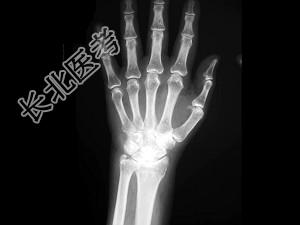

- 单项选择题女,50岁, 手指关节肿痛,晨僵, 结合图像,最可能诊断是 ( )

A、关节结核

B、牛皮癣性关节炎

C、痛风性关节炎

D、类风湿关节炎

E、Reiter综合征